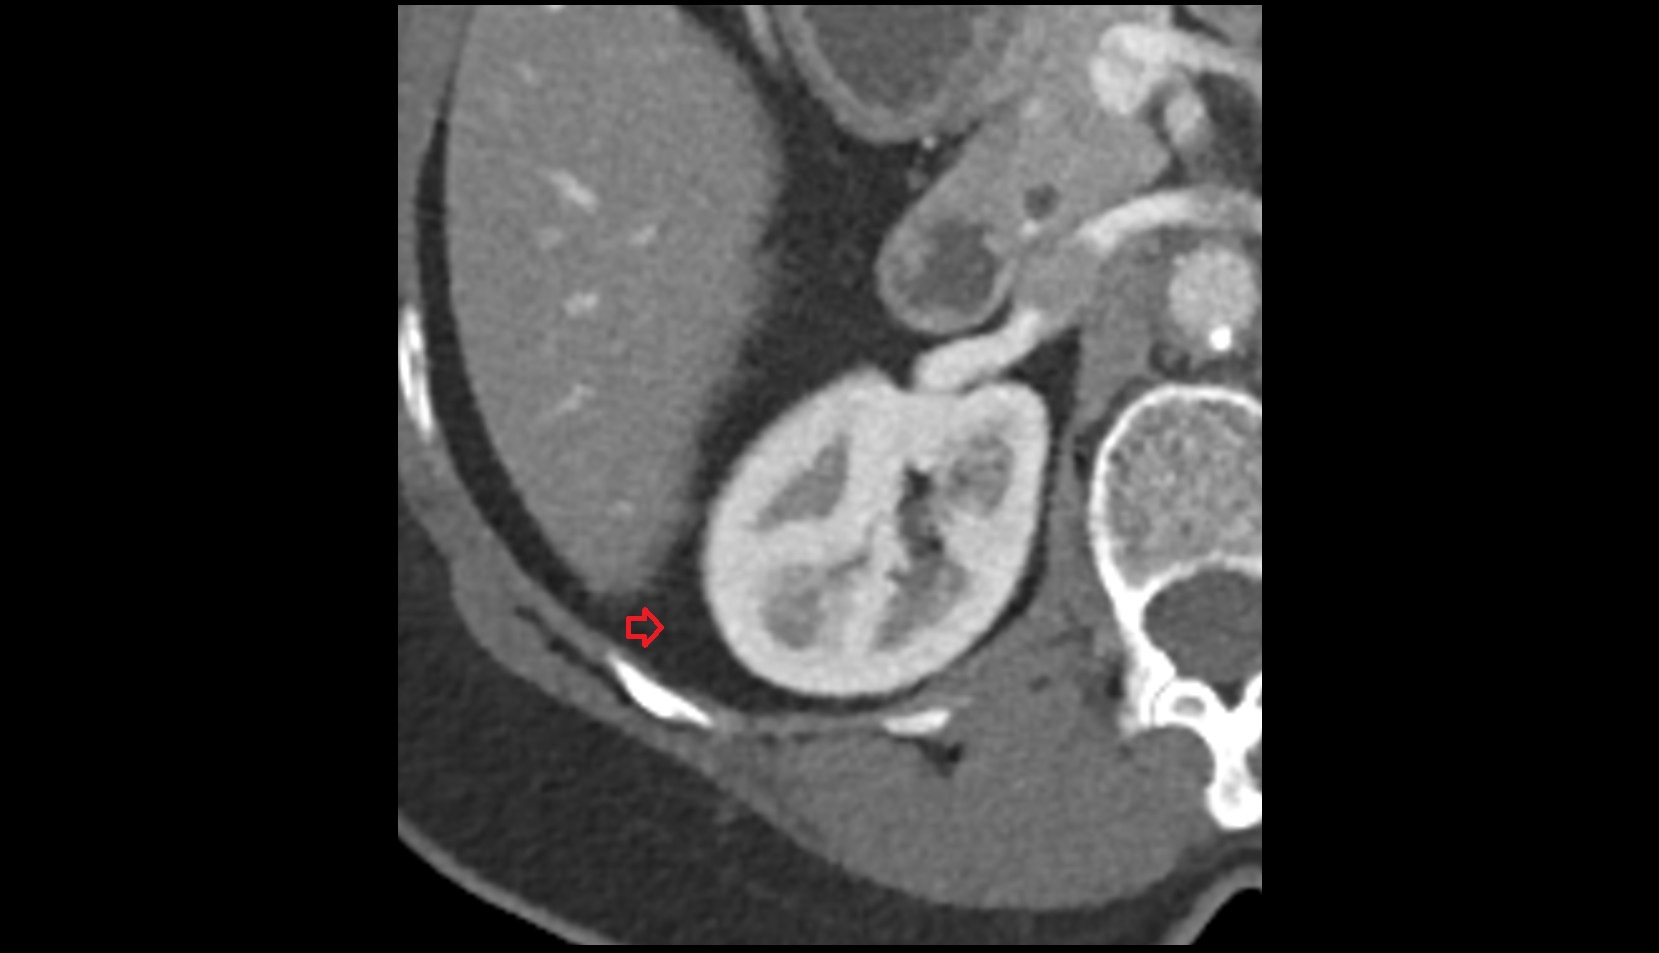

- kidneys

- Right kidney

- Left kidney

- Kidney cortex (Renal cortex)

- Renal capsule

- Renal medulla

- Renal pyramids

- Renal fascia

- Renal artery

- Renal vein